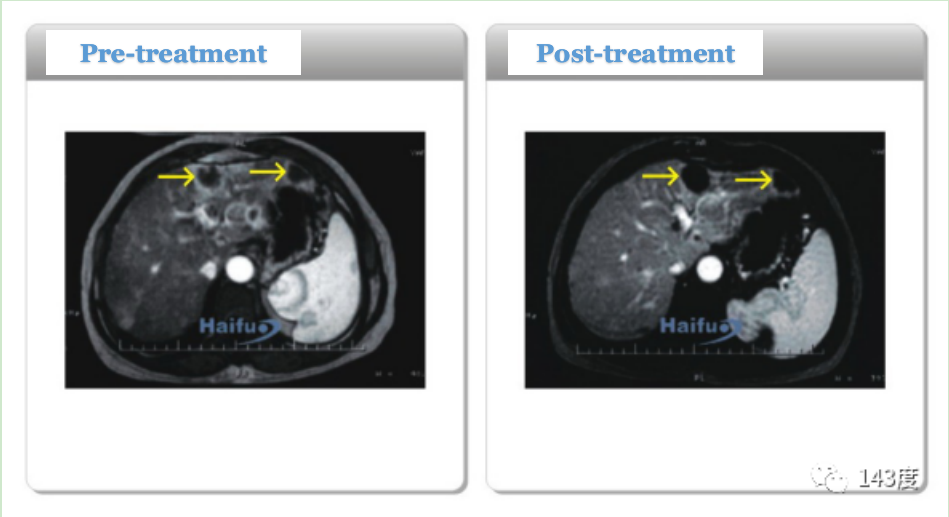

Pancreatic Cancer Treatment Case 4:

Patient: Female, 57 years old, pancreatic cancer

Tumor necrosis occurred 3 days after HIFU treatment. The tumor shrank by 28.7% at 6 weeks, 66% at 3 months, and pain was completely relieved.

Pancreatic Cancer Treatment Case 5:

Patient: Female, 41 years old, pancreatic cancer

After 9 days of HIFU treatment, a follow-up PET-CT scan showed extensive necrosis at the center of the tumor.